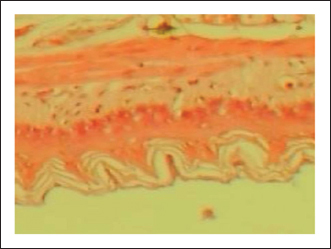

The gastric tissue slides were examined under a microscope for morphological changes such as hyperemia, hemorrhage, edema, necrosis, inflammatory changes, distortion, erosion, and ulcers caused by the destructive effects of indomethacin on stomach tissues. No pathological changes were observed in the normal control group (Fig. 1). Rats in the ulcer control group showed significant damage to the surface epithelium, necrotic areas penetrating the mucosal layer, and severe edema of the submucosal layer. Additionally, there was congestion with infiltration of inflammatory cells (Fig. 2). Histological results revealed that the treated rats with ranitidine had less protection of the gastric lining due to mild infiltration of leucocyte and edema in the submucosal layer, in addition to less disruption in both the superficial and deep mucosal layers. Treatment doses (300, 400 and 500 mg/kg) with P. farcta extract. Groups treated with P. farcta extract (300 and 400 mg/ kg) showed mild infiltration of inflammatory cells, edema, or significant disruption of the deep mucosa (Figs 5 and 6) while, P. farcta extract group (500mg/ kg) prevented histological changes and showed no infiltration of inflammatory cells, edema, or significant disruption of the deep mucosa (Figs 3, 4 and 7).

Fig. 2. Normal control group received distilled water, No pathological changes were observed.

Fig. 4. Standard drug group (ranitidine) mild infiltration of leucocyte and less edema in the sub-mucosal layer.